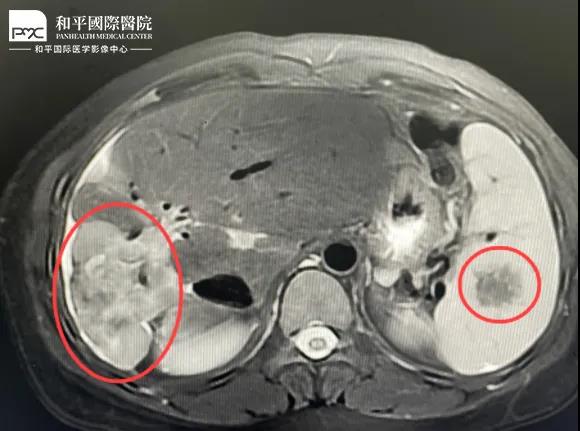

檢查結(jié)果對(duì)于這家人而言猶如晴天霹靂,經(jīng)核磁共振等相關(guān)檢查,當(dāng)?shù)蒯t(yī)生懷疑是肝癌,建議手術(shù)治療。悲痛中,家人們對(duì)這樣的結(jié)果表示無(wú)法接受,想要多去幾家醫(yī)院看看,為了進(jìn)一步確診,王小姐來(lái)到我院醫(yī)學(xué)影像中心進(jìn)行檢查,事情竟發(fā)生了戲劇性反轉(zhuǎn)。

根據(jù)影片分析,結(jié)合王小姐有系統(tǒng)性紅斑狼瘡的病史,長(zhǎng)期服用激素,免疫力低下,近期又有低熱盜汗的癥狀,影像中心執(zhí)行主任侯文杰初步判斷王小姐是得了肝結(jié)核,并不是肝癌!

由于肝結(jié)核是臨床非常少見(jiàn)的病例,單靠影像診斷是很難診斷正確的,在侯主任的建議下,王小姐做了穿刺活檢,診斷結(jié)果的確是肝結(jié)核。